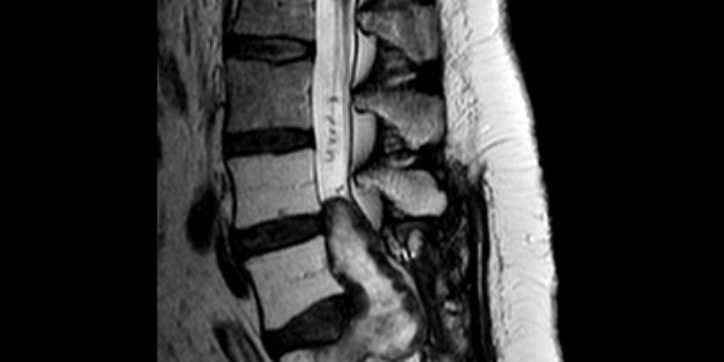

Ασθενής 55 ετών με γνωστή εκτεταμένη εξεργασία (όγκος) του ιερού οστού. Είχε προηγηθεί προσπάθεια αφαίρεσης της βλάβης. Κλινικά η ασθενής παρουσίαζε προοδευτική επιδείνωση της κλινικής της εικόνας με ισχιαλγία, οσφυαλγία και διαταραχές στον έλεγχο της κύστης και του εντέρου. Από τον απεικονιστικό έλεγχο διαπιστώθηκε ευμεγέθης εξεργασία ιερού με σημαντική πίεση στα νεύρα της ιππουρίδας καθώς επίσης και σημαντική οστεόλυση του Ο5 σπονδύλου και του ιερού οστού.

Αποφασίστηκε η διενέργεια αρχικά σπονδυλόδεσίας της κατώτερης οσφυικής μοίρας με το ιερό οστό και τα λαγόνια. Στη συνέχεια ακολούθησε ολική εξαίρεση του όγκου (σβάννωμα)

Πρώτον, υπάρχει σημαντικό πρόβλημα στήριξης της οσφυϊκής μοίρας και επαπειλούμενο κάταγμα ιερού. Λόγω της διήθησης του οστού από τον όγκο, έχει δημιουργηθεί σημαντικό οστικό έλλειμα στον τελευταίο οσφυϊκό σπόνδυλο και στο ιερό οστό.